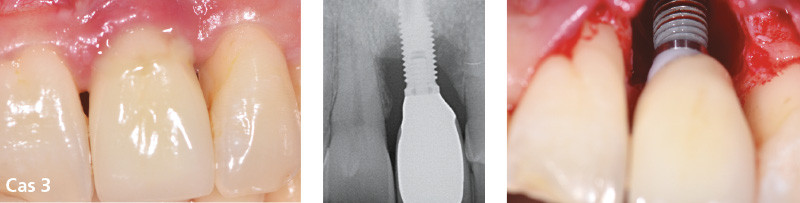

Les péri-implantites avancées : traiter ou déposer ?

Les péri-implantites sont pour la plupart asymptomatiques et le diagnostic est souvent tardif. Le praticien est donc confronté à des pertes osseuses péri-implantaires souvent sévères pouvant représenter plus de la moitié de la hauteur de l’implant. De plus, la morphologie des lésions osseuses associées peut être plus ou moins complexe.

La régénération autour des implants, décrite dans la littérature et faisant l’objet de nombreuses conférences parfois spectaculaires, n’est pas toujours prédictible et dépend de multiples facteurs [6-8].

Il est donc logique de se poser la question, face à une péri-implantite sévère, de la conservation ou de la dépose de l’implant atteint. Il n’existe aujourd’hui dans la littérature aucun arbre décisionnel concret pour cette prise de décision : traiter ou déposer ?